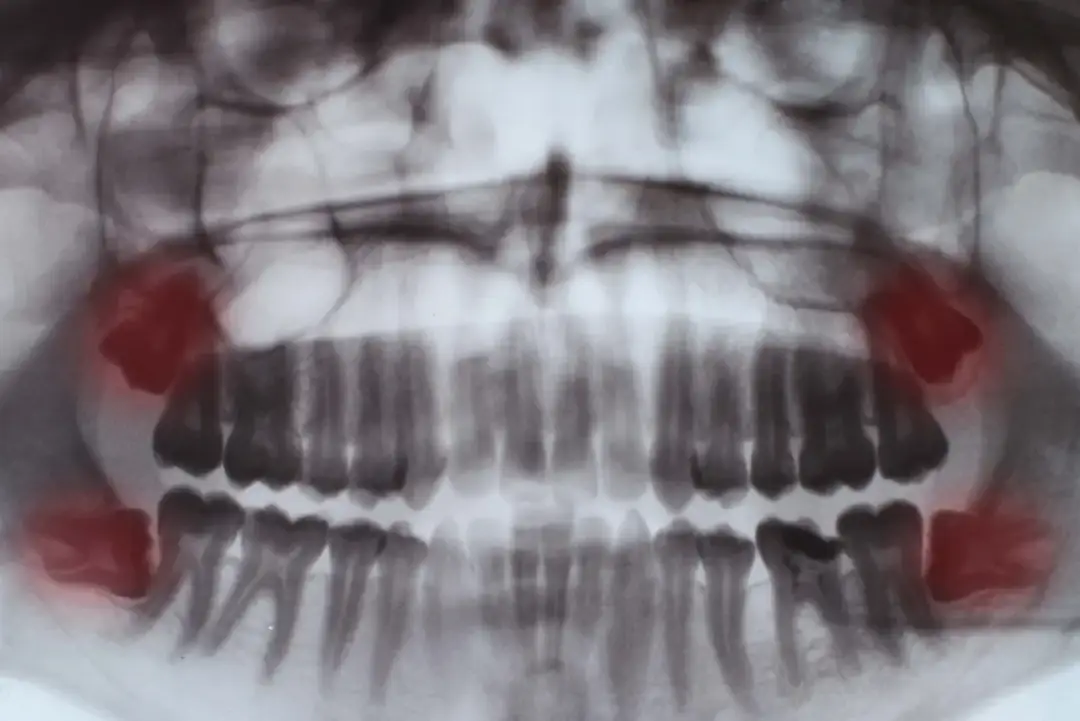

Dowiedz się, kiedy rosną zęby mądrości (17-25 lat), jakie objawy towarzyszą ich wyrzynaniu i jak radzić sobie z bólem. Sprawdź, kiedy wizyta u dentysty jest konieczna.